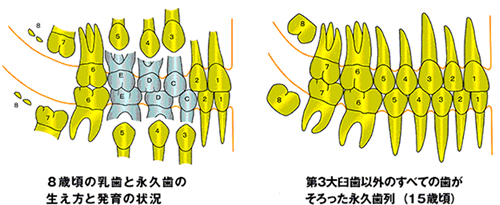

顎関節症の病気の状態(病態)は現在4つに分類されています。最も多いのは関節内にある関節円板(図1)というクッションが前方にずれることで起きる「カクンカクン」という音が出る状態(図2)、あるいはずれがもっと大きくなることで大きな口が開けられなくなる状態です(図3)。

特に口が大きく開かなくなると、口を開けたり食品をかもうとするときに痛みが出ます。

この2つの状態で来院される方が全体の60%ほどになります。

これ以外では顎関節そのものには痛みがないのですが、下顎を動かす筋肉がうまく働かなくなり、口を開けようとすると頬やこめかみの筋肉が痛むという状態(図4)、あるいは関節円板のずれはないのですが、口を開けようとすると顎関節が痛む捻挫に似た状態があります。

4番目はこれまでの3タイプほどは多くありませんが、関節を作っている骨が変形するタイプの顎関節症があります。

このタイプは長年顎関節症が続いていたり、年齢の高い方に多くみられます(図5)